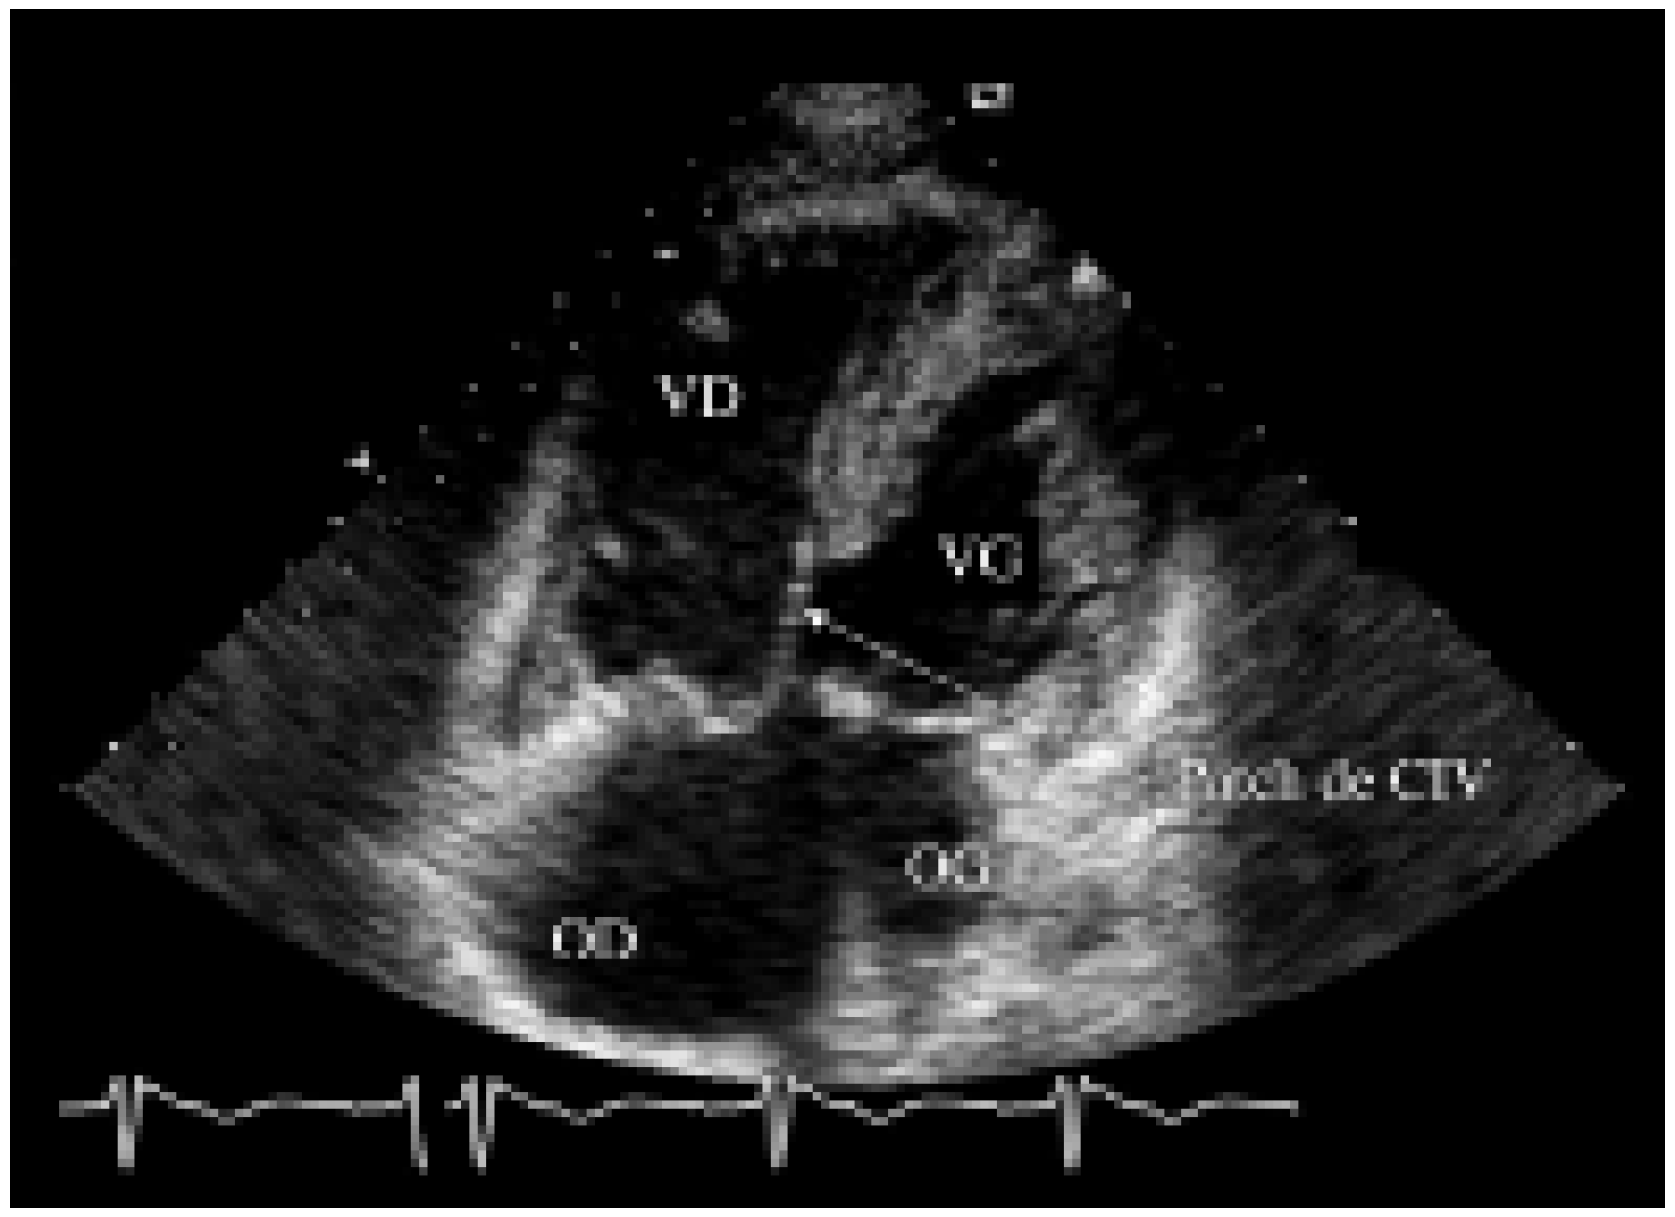

Présentation de cas